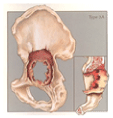

Right acetabular cup mobilization 10 years postoperative (figure 5).

Figure 5. Case 3 - Paprosky Type 2b

Defects are characterized by a deficient superior dome, allowing for superior and lateral component migration owing to the lack of a lateral stabilizing buttress, normally provided by the lateral margin of the superior dome.